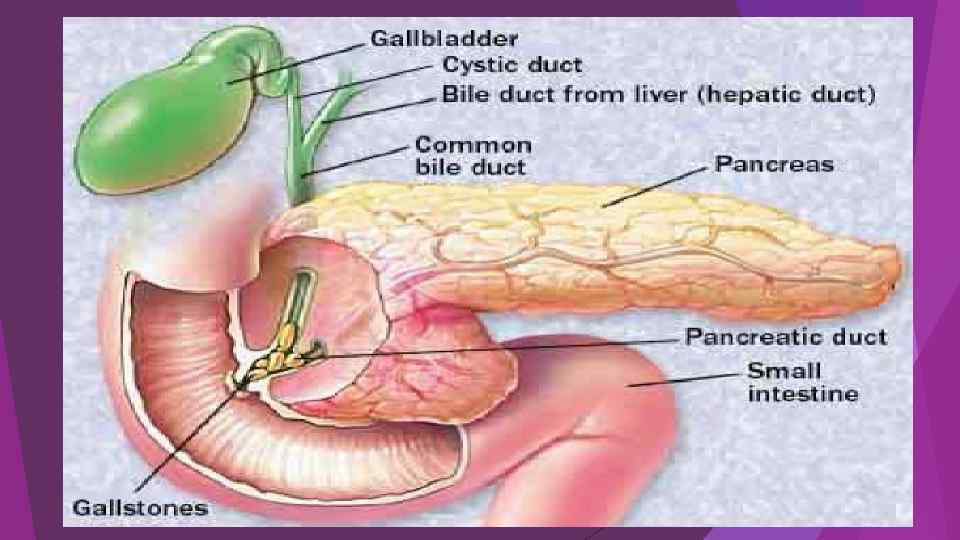

Острая блокада терминального отдела холедоха (острый панкреатит)

Острая блокада терминального отдела холедоха (острый панкреатит)

Acute pancreatitis and pseudocyst. A 63 -year old woman admitted with gallstonerelated pancreatitis.

Acute pancreatitis and pseudocyst. A 63 -year old woman admitted with gallstonerelated pancreatitis.